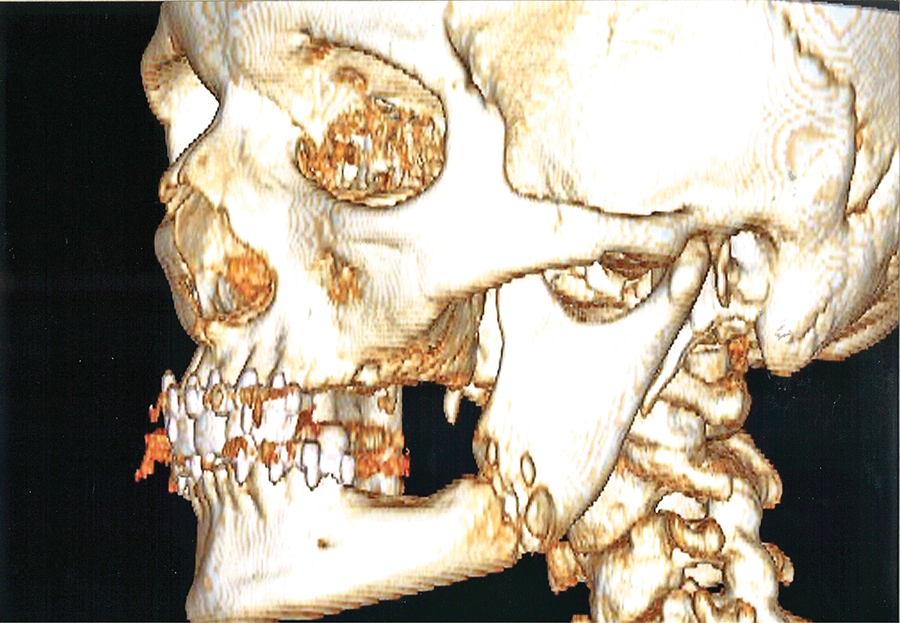

Substantial public and private resources are spent on the prevention and management of infections. Public health campaigns around the world have made considerable gains in the improvement of hygiene practices and disease prevention. Specific strategies have been employed, including water fluoridation that have significantly reduced dental decay. Significant efforts are directed at reducing the incidence … Read more